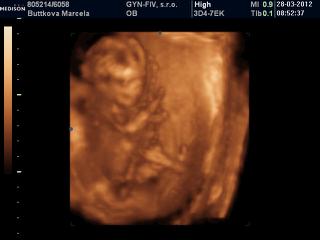

Ahojte,

toto som našla🙂

@marcelatje jééééj.......už aj ja chcem ísť na usg 🙂

@vladka1828 mám aj krajšie fotečky, ale akosi mi tie čísla fotiek v prezentácii nesedia s číslami fotiek na CD tak sem dalo úplne iné ako som chcela 😒 Každopádne to bol zážitok a vrelo každému odporúčam 🙂

@marcelatje nevadí, aj tieto sú pekné 😉 ja by som na to asi pozerala deň-noc 🙂 mne vždy slza vyskočí aj pri normálnom usg, minule keď som videla ako si pekne kopkalo nožkami - taká som bola šťastná 🙂

@marcelatje jéj,a aj pohlavie ste sa dozvedeli???

@vladka1828 bolo to naozaj neopísateľné, úplne iné ako keď nad tým bábätkom len rozmýšľaš, keď vidíš ako sa hýbe a prejavuje sa no krása 🙂

@tomika pohlavie nevieme, dokina síce povedala že tipuje dievčatko, ale že to máme brať s veľkou rezervou, lebo za prvé je ešte skoro a za druhé bábätko bolo celý čas opreté o stenu maternice a obraz nebol celkom jasný. Povedala že to môže byť kľudne aj chlapček tak sme tam kde sme aj boli 🙂

@marcelatje zlatučké je Tvoje maličké 🙂